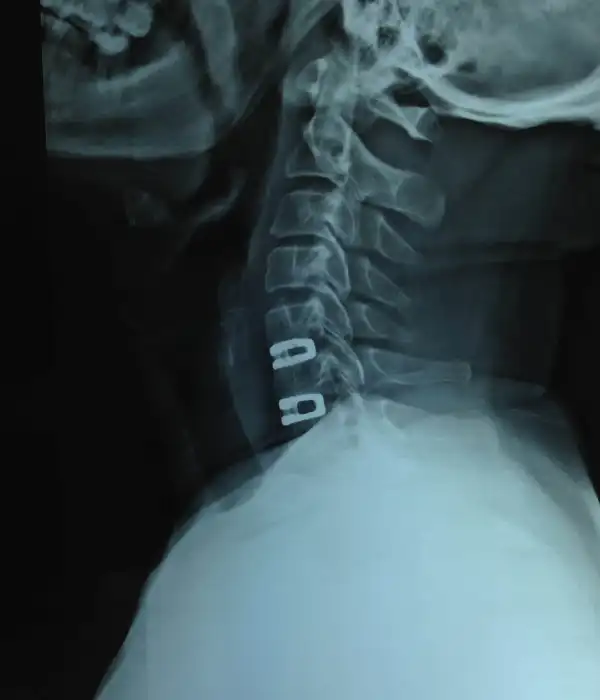

C1-C2 instability Post OP X ray

C1-C2 fusion Post OP X ray